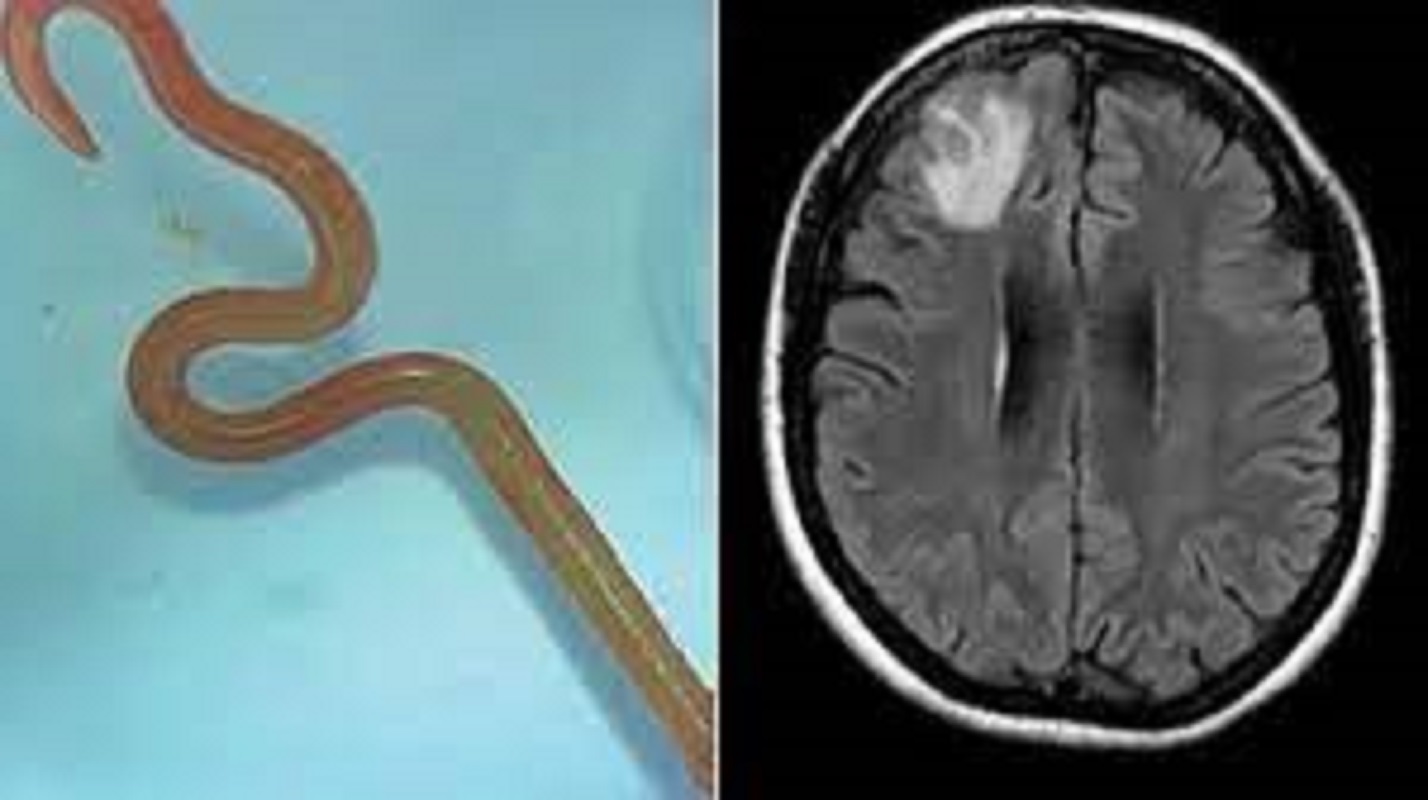

Un neurochirurgo ha raccontato di aver prelevato un verme dal cervello di una paziente mentre indagava sui misteriosi sintomi che l’avevano colpita. Dopo aver eseguito la biopsia Hari Priya Bandi ha estratto con una pinza il parassita che misurava 8 centimetri all’ospedale di Canberra, in Australia.

Il verme misurava 8 centimetri ed è stato scoperto dal neurochirurgo Bandi mentre eseguiva una biopsia a Canberra

“Ho solo pensato: ‘Che cos’è? Non ha alcun senso. Ma è vivo”. Bandi è stato citato martedì nel quotidiano The Canberra Times. “Ha continuato a muoversi con vigore. Ci siamo sentiti tutti un po’ male” – ha aggiunto Bandi parlando della sua squadra operativa. La creatura era la larva di un nematode nativo australiano non precedentemente noto come parassita umano, chiamato Ophidascaris robertsi. I vermi si trovano comunemente nei pitoni tappeto.

Senanayake ha detto che la biopsia cerebrale avrebbe dovuto rivelare un cancro o un ascesso. “Questo paziente era stato curato… per quella che era una malattia misteriosa”. Bandi ha spiegato che la sua paziente ha ripreso conoscenza dopo che il verme è stato estratto senza alcuna conseguenza negativa. “Era così grata di avere una risposta per ciò che le aveva causato problemi per così tanto tempo”.